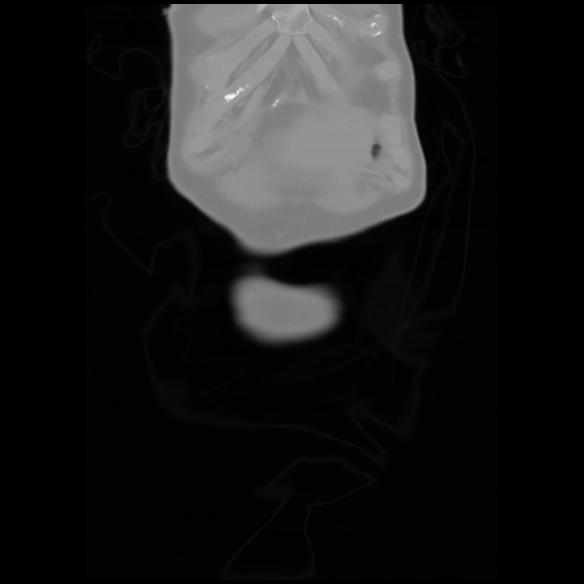

6 CUERPO,CE,Coronal,3.000,CUERPO,Coronal,